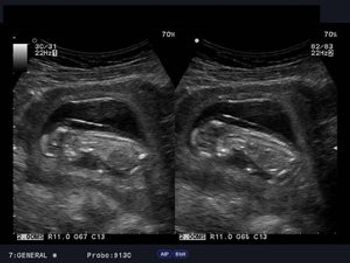

This is the case of a pregnancy at 12 weeks gestational age. The patient underwent routine prenatal transabdominal and transvaginal ultrasound imaging.